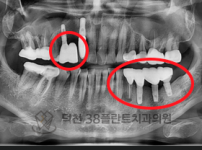

치료전후